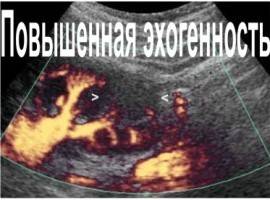

Несмотря на то, что звучит это слово довольно пугающе, при выявлении повышенной эхогенности не стоит сразу придумывать себе какие-либо тяжелые заболевания. Эхогенная плотность — важный показатель при проведении исследования. Говоря проще, это способность отражать звук, который затем обрабатывается в картинку. Ее-то мы и можем видеть на экране во время ультразвукового исследования. Повышенная эхогенность говорит о том, что ткани отражают звук очень хорошо (на экране они выглядят как светлые участки).

Все органы в нашем организме важны, и каждый из них выполняет определенные функции. Печень считается жизненно необходимым органом, основная функция которого — фильтрация и очистка крови от вредных элементов. К сожалению, далеко не у каждого человека получается тщательно следить за своим здоровьем, и такой важный механизм дает сбой. Употребление алкоголя, лечение некачественными лекарственными препаратами, неправильное питание… Все это значительно влияет на наше самочувствие и на состояние печени. Если в ее работе начнется сбой, она будет вам подавать сигналы в виде колик, тошноты, тяжести. После таких настораживающих признаков следует в больнице сделать УЗИ. Как правило, в результате врач может поставить диагноз, что эхогенность печени повышена. Несмотря на то что звучит такое словосочетание достаточно пугающе, при выявлении болезни не стоит паниковать и придумывать себе смертельное заболевание. Эхогенная плотность – это показатель, на котором основывается исследование органов с помощью УЗИ. Проще говоря, это отражение звука, которое обрабатывается в изображение. Именно его мы имеем возможность увидеть на специальных экранах во время обследования. Если ваш врач сказал, что эхогенность печени повышена, то это свидетельствует о том, что ткани органа очень хорошо отражают звук (на мониторе это будет выглядеть в виде белых пятен), то есть замечено явное нарушение работы органа. Давайте разберемся, что означает и поддается ли лечению такой диагноз?

Эхогенность визуализируется на экране монитора. При гиперэхогенности орган становится видимым, как оттенки белого цвета, гипоэхогенность – это различные оттенки темного цвета вплоть до черного. Изоэхогенность проявляется серым цветом печени на мониторе и является вариантом нормы.